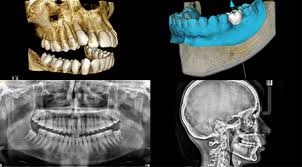

A fogászatban a képalkotó diagnosztika csúcsát a 3D fogászati CT berendezések képviselik. Precizitásuk, illetve az általuk elérhető információ össze sem hasonlítható a kétdimenziós röntgendiagnosztikai eljárásokkal.

Az implantációs beavatkozásoknál különös jelentőséggel bír a pontos tervezhetőség.

Amellett, hogy a műtét menete a CT segítségével tökéletesen lemodellezhető, a beavatkozás költségvonzata is könnyebben behatárolható.

Természetesen a kontrollvizsgálatok és a fogszabályozás diagnosztikája során a mai napig készítünk digitális panoráma és teleröntgen felvételeket is.